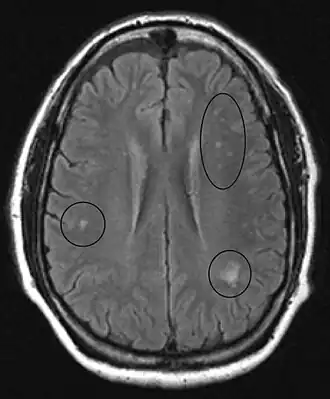

In the brain itself, changes are less severe: They occur as small sources of nervous fibers decay and accumulation of astrocytes, usually subcortically located, and also round hemorrhages with a torus of glial cells.

MRI of the brain may show periventricular white matter abnormalities. MRI of the spinal cord may show linear hyperintensity in the posterior portion of the cervical tract of the spinal cord, with selective involvement of the posterior columns.